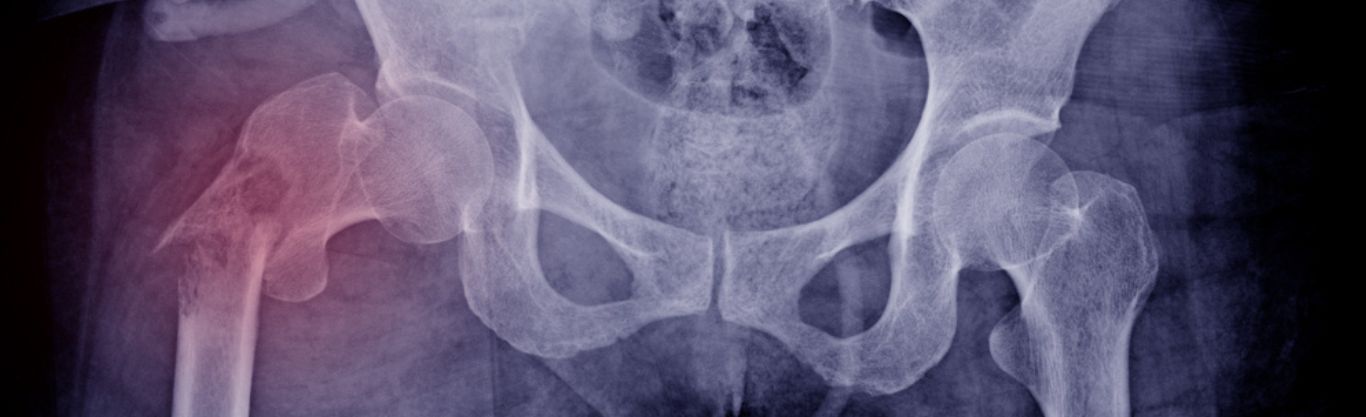

• Osteoporosi: è una condizione caratterizzata da una riduzione della densità minerale ossea, che rende le ossa fragili e suscettibili a fratture anche in occasione di traumi di lieve entità. Colpisce principalmente le donne dopo la menopausa e gli anziani.

• Radiografie per evidenziare eventuali deformità ossee o microfratture.